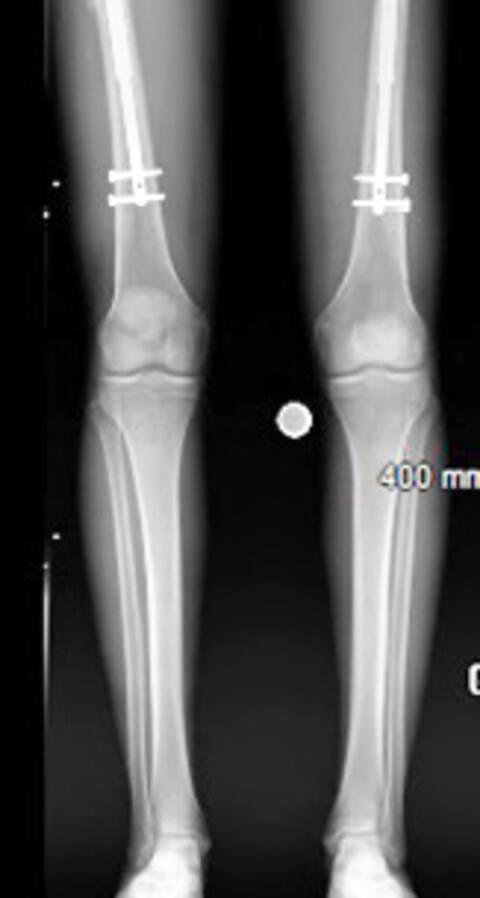

Surgery involves breaking two femurs or two tibiae (at the patient’s discretion) to insert a steel nail. After that, the patient uses a magnetic machine that rotates the nail one millimeter a day. For several months, the patient should undergo physiotherapy on a daily basis.

“The bone heals well. But, stretching affects the muscles more. They need to stretch,” T explainsRe. Bending the knee or waist is sometimes very difficult. If we say no to the body, we stop. But most reach seven or eight centimeters. They are highly motivated. “

Patients get tibia and two femurs stretched, 15 cm. Generally, patients recover within a year.